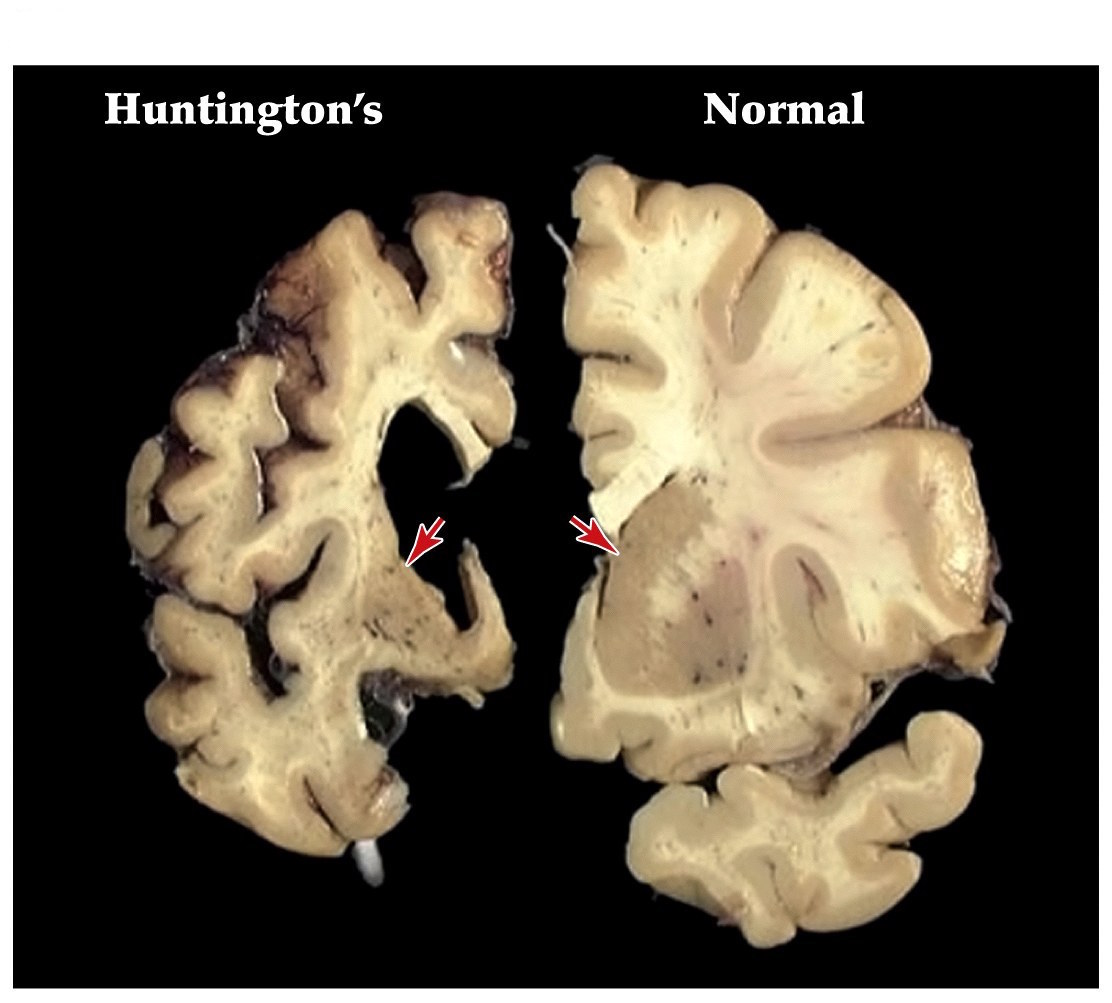

Huntingtons disease

• One of the most common inherited neurological diseases

• Progressive deterioration of the caudate and putamen that project to the GP externa (indirect pathway)

• Leads to a movement disorder consisting of rapid jerky motions with no clear purpose

Neuroscience 5e Fig. 18.9

Note:

• George Huntington, physician long island 1872

• 1 in 10000 people will have Huntington's disease in the US

• death in 10-20 yrs

• autosomal dominant inheritance, chromosome 4. Gene called Huntingtin

• if disease begins in childhood rigidity, seizures, dementia, and rapid progressive course can ensue

• atrophy of striatum is pronounced. Some associated degeneration of frontal and temporal cortices

Function of huntingtin gene product unclear. Null expression in mice lethal

• Dominantly inherited strikes around midlife

• Patients develop depression, mood swings, and abnormal movements (striatum)

• Caused by alterations in a single gene that encodes the huntingtin protein

• Huntingtin protein has an expansion of a CAG trinucleotide repeat, resulting in an extended polyglutamine repeat. Leads to aggregation of proteins and cell death

15-34 cytosine-adenine-guanine (CAG) DNA repeats normally, 42-66 in Huntingtin's disease resulting in an unstable triplet repeat in coding region of gene. Polyglutamine

Hypokinetic and hyperkinetic disorders summary

• Parkinson's hypokinetic disorder. More tonic inhibition of thalamus and decreased excitation of frontal cortex

• Huntington's hyperkinetic disorder. Less tonic inhibition of thalamus and more excitation of frontal cortex